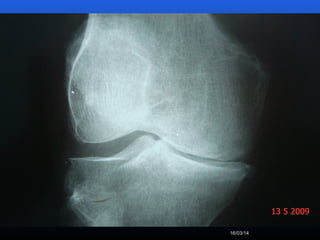

RADIOLOGIA

No início da doença não se observam anormalidades.

Com seu desenvolvimento, observam-se:

 Diminuição do espaço intra-articular

 Esclerose subcondral (eburnação)

 Osteófitos;

 Erosão e anquilose óssea (pseudocistos ósseos).

RADIOLOGIA No início dadoença não se observam anormalidades. Com seu desenvolvimento, observam-se:  Diminuição do espaço intra-articular  Esclerose subcondral (eburnação)  Osteófitos;  Erosão e anquilose óssea (pseudocistos ósseos).